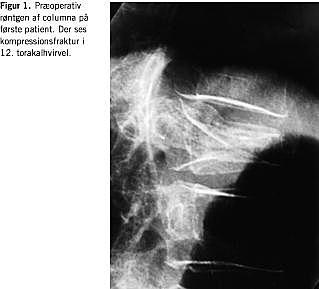

Gennemlysningsvejledt og i infiltrationsanalgesi indførtes en knoglebiopsikanyle gennem den venstre pedikel frem til overgangen mellem den forreste og midterste tredjedel af corpus i sagittalplanet. Til at sikre kanylens placering og vurdere overløb til vena cava eller spinalkanalen injiceredes 2 ml iodixanol under kontinuerlig røntgengennemlysning. 3 ml Simplex P tilsat bariumsulfat blev derefter indsprøjtet, stadig under gennemlysning. På grund af manglende overflow af knoglecement henover midtlinjen i frontalplanet blev proceduren gentaget i den højre pedikel. Patienten blev efter en time mobiliseret og den efterfølgende dag udskrevet smertefri til hjemmet. Ved en radiologisk og klinisk kontrol tre måneder post-operativt var patienten fortsat i velbefindende, men knoglecementen var radiologisk displaceret anteriort (Figur 2 ).